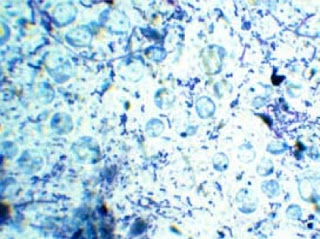

La forma quística se ha descrito hace pocos años posiblemente debido a que su pequeño tamaño (3-5 μm) y apariencia hacían considerarlos como artefactos. Existen 2 tipos de quistes: fecales (forma infectante, transmisible) o de pared gruesa y quistes de pared fina responsables de la autoinducción.

Los quistes fecales son esféricos u ovoides y están protegidos por para pared multilaminar. Poseen de 1 a 4 núcleos, múltiples vacuolas y depósitos lipídicos y de glucógeno. Están rodeados por una capa fibrilar independiente que parece producida por el organismo cuando madura.

El diagnóstico es directo y se basa en la detección microscópica de quistes y/o formas vacuolares en heces. Las formas vacuolares se observan con menor frecuencia si se utilizan técnicas de concentración debido a su mayor labilidad.

Pleomorfismo de Blastocystis hominis